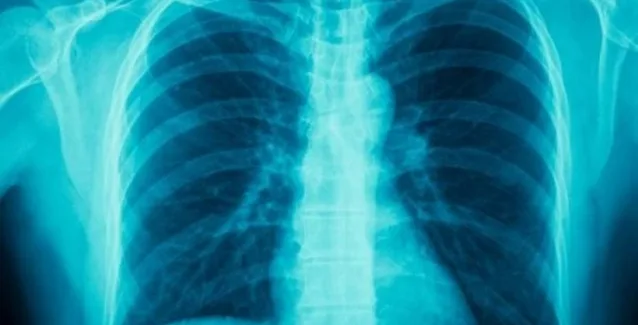

Μονόδρομο χαρακτηρίζει την αποτελεσματική εφαρμογή της εγκυκλίου για την καθολική απαγόρευση του καπνίσματος, σε επιστολή της προς τους αρμόδιους φορείς, η Ελληνική Πνευμονολογική Εταιρεία, τονίζοντας πως αποτελεί καθοριστικό παράγοντα για την αντιμετώπιση των χρόνιων πνευμονοπαθειών, για τη βελτίωση της ποιότητας ζωής των πολιτών αλλά και για την εξυγίανση του Εθνικού Συστήματος Υγείας.

«Αν οι πολίτες σταματούσαν το κάπνισμα, σε 20-30 χρόνια χρόνιες πνευμονοπάθειες όπως η Χρόνια Αποφρακτική Πνευμονοπάθεια (ΧΑΠ) θα είχαν μειωθεί ή ακόμη και εξαφανιστεί, ενώ σήμερα αποτελούν την » επισημαίνει ο πρόεδρος της Ελληνικής Πνευμονολογικής Εταιρίας (ΕΠΕ), κ. Μιχάλης Τουμπής, στην επιστολή προς τους υπουργούς Υγείας και Δημόσιας Τάξης καθώς και προς τον πρόεδρο της Βουλής, χαιρετίζοντας την έκδοση της εγκυκλίου για την καθολική απαγόρευση του καπνίσματος.

Δυστυχώς στη χώρα μας οι αριθμοί, παρά τις όποιες προσπάθειες εφαρμογής της νομοθεσίας, εξακολουθούν να είναι απογοητευτικοί σχετικά με τη μείωση ή τη διακοπή της καπνιστικής συνήθειας. Τα στοιχεία που παραθέτει το Δ.Σ της Ελληνικής Πνευμονολογικής Εταιρείας είναι θλιβερά: «το 35%-45% των Ελλήνων καπνίζουν ενώ στα ανεπτυγμένα κράτη το αντίστοιχο ποσοστό κυμαίνεται από 15% έως 20%. Παράλληλα τα ποσοστά των ασθενών με χρόνιες πνευμονοπάθειες, όπως η Χρόνια Αποφρακτική Πνευμονοπάθεια (ΧΑΠ) εξαιτίας του τσιγάρου αυξάνονται δραματικά τα τελευταία χρόνια.

To 10,6% των Ελλήνων πάσχει από ΧΑΠ, γνωστή και ως νόσο των καπνιστών, καθώς η επίπτωση της συνδέεται ευθέως με την επίπτωση της καπνιστικής συνήθειας. Επειδή η ΧΑΠ σχετίζεται άμεσα με την καπνιστική συνήθεια, ο επιπολασμός της μπορεί να μειωθεί κυρίως με τον αποτελεσματικό έλεγχο του καπνίσματος. Στις ανεπτυγμένες χώρες η ΧΑΠ οφείλεται στο κάπνισμα, ενεργητικό και παθητικό. Στη χώρα μας ευθύνεται για το 13% των νοσηλειών ενώ το 56% αυτών που πάσχουν δεν το γνωρίζουν. Κάθε ασθενής με ΧΑΠ κοστίζει 5.600 ευρώ ετησίως».